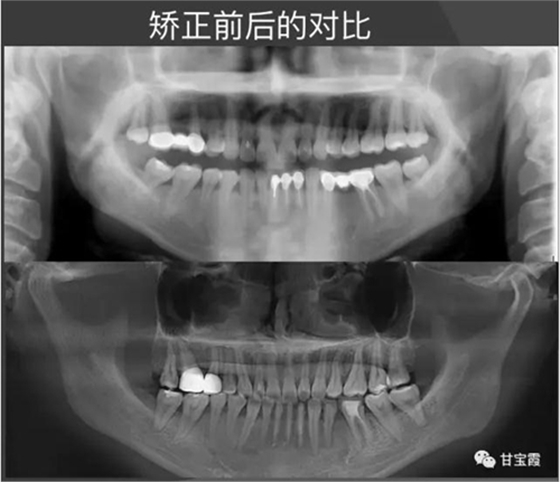

經(jīng)過(guò)28個(gè)月的矯正,大家可以看到原來(lái)的兩個(gè)缺牙間隙沒(méi)有了,舊的烤瓷牙換成了全瓷冠修復(fù)。下面的圖片是矯正前后的X線對(duì)比,

下圖是矯正前后的開(kāi)口頜像的對(duì)比,患者朋友看到這么好的治療效果,很后悔幾年前做的烤瓷修復(fù),還白白的磨了好牙。